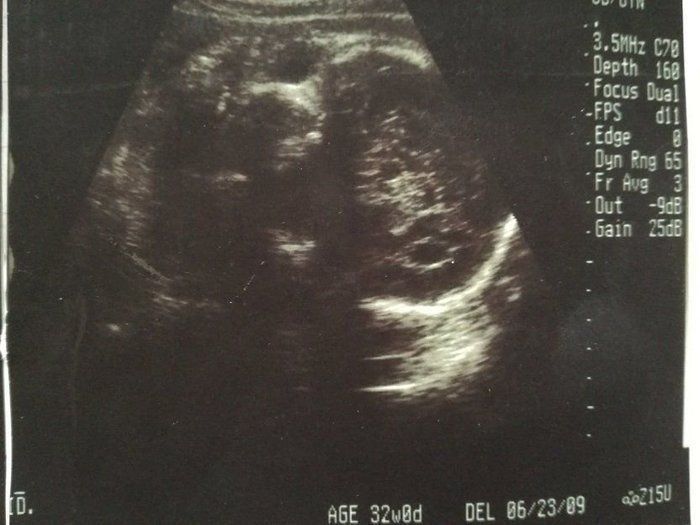

チャーミー小結さんの妊娠32週目のエコー写真

命の始まりは神秘的!2D・3D・4Dのエコー写真で見る「私と赤ちゃんの実録260日」

妊娠32週目。赤ちゃんの体重1915g。この頃の楽しみは医師軍団による回診で、ドラマ「白い巨塔」の再現VTRを見ているようでした。実家の母に頼んでウエストサイズ100cmのパジャマを作って送ってもらいました。